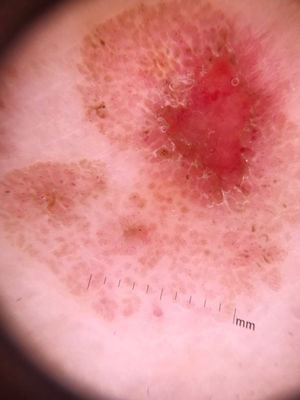

Ao exame dermatológico, observou‐se uma placa rósea levemente elevada com limites irregulares, porém evidentes e com pequena área de exulceração (fig. 1). À dermatoscopia era possível observar, além da exulceração, várias estruturas arredondadas marrons e bem delimitadas, circundadas por vasos em ponto (figs. 2 e 3).

No caso relatado encontramos a presença de vasos em ponto distribuídos em círculo ao redor de estruturas arredondadas e amarronzadas. Representa, na correlação da dermatoscopia com a histopatologia, proliferação de vênulas próximo aos blocos de células clonais. Vasos em ponto, quando em lesões que não sejam melanocíticas, são inespecíficos, porém o padrão encontrado na lesão descrita pode ser peculiar.6 Já as estruturas arredondadas representam os ninhos de células clonais intraepidérmicos melanizadas, correspondem ao FBJ. Embora na coloração de hematoxilina e eosina não pudesse ser vista a presença do pigmento, quando feita a coloração de Fontana‐Masson observou‐se grande quantidade de melanina nos blocos (fig. 5).